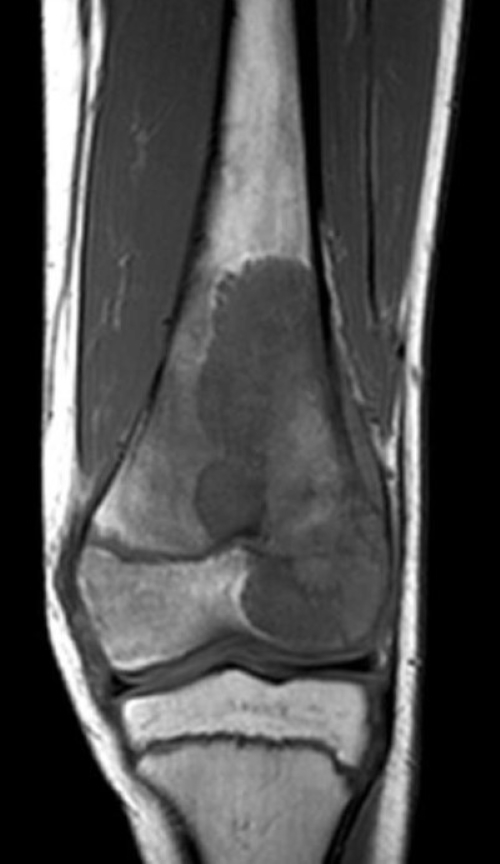

MRT Knie Frontalansicht

Eine MRT Knie ist eine der häufigsten durchgeführten MRT-Untersuchungen. Schmerzen im Knie können viele Gründe haben, da das Knie aus einem Gelenkkomplex besteht. Diesen Gelenkkomplex kann man in einer Knie MRT detailliert darstellen, um präzise Diagnosen zu erzielen. Das Knie kann Verletzungen insbesondere beim Sport, aber auch im Alltag erleiden.

Zudem ist es möglich, Aussagen über den Zustand des Meniskus (Knorpel zwischen Oberschenkelknochen und Schienbein), der Bänder und des Knorpels des Kniegelenks zu machen, sowie die Intaktheit der Sehnen, Muskulatur und Knochen abzuklären.

Kniearthrose lässt sich im Rahmen einer MRT-Untersuchung ebenfalls genauer analysieren. Sind sogenannte „weiße Stellen“ im MRT zu erkennen, handelt es sich hierbei möglicherweise um Zeichen einer Flüssigkeitsansammlung und könnte ein Hinweis auf ein Knochenmarködem sein.